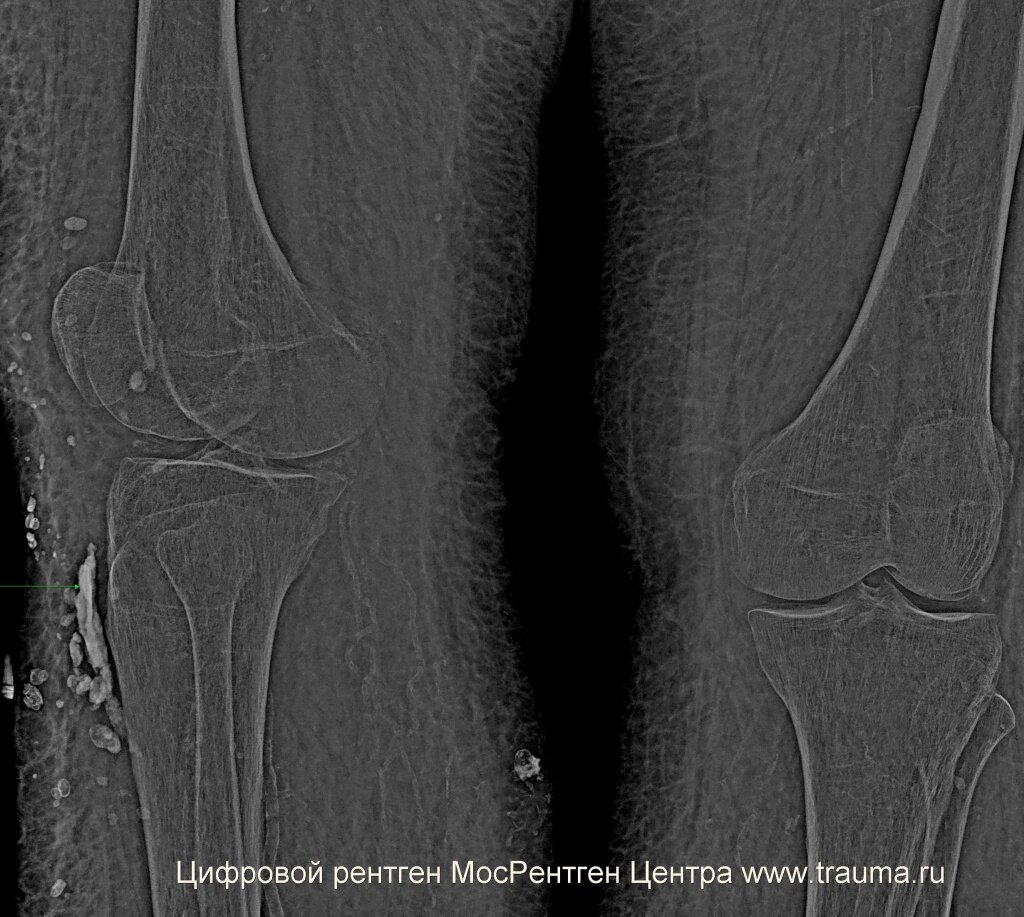

При сохранении сильной боли нужно проконсультироваться у травматолога и сделать рентгенограммы в двух проекциях для исключения перелома костей. Рентген позволяет определить, есть или нет перелом с вероятностью до 99%. Если есть подозрение на перелом, а рентген этого не определяет, можно выполнить компьютерную томографию с построением трехмерного объекта. При повреждении мягких тканей более эффективна магнитно-резонансная томография (МРТ). Какую методику более эффективно применить в каждом случае? Это решает врач.

При сильном ушибе под кожей могут образоваться сгустки крови - гематомы. Некоторые из них могут уплотняться и при ощупывании чувствоваться под кожей. Гематома показана зеленой стрелкой.